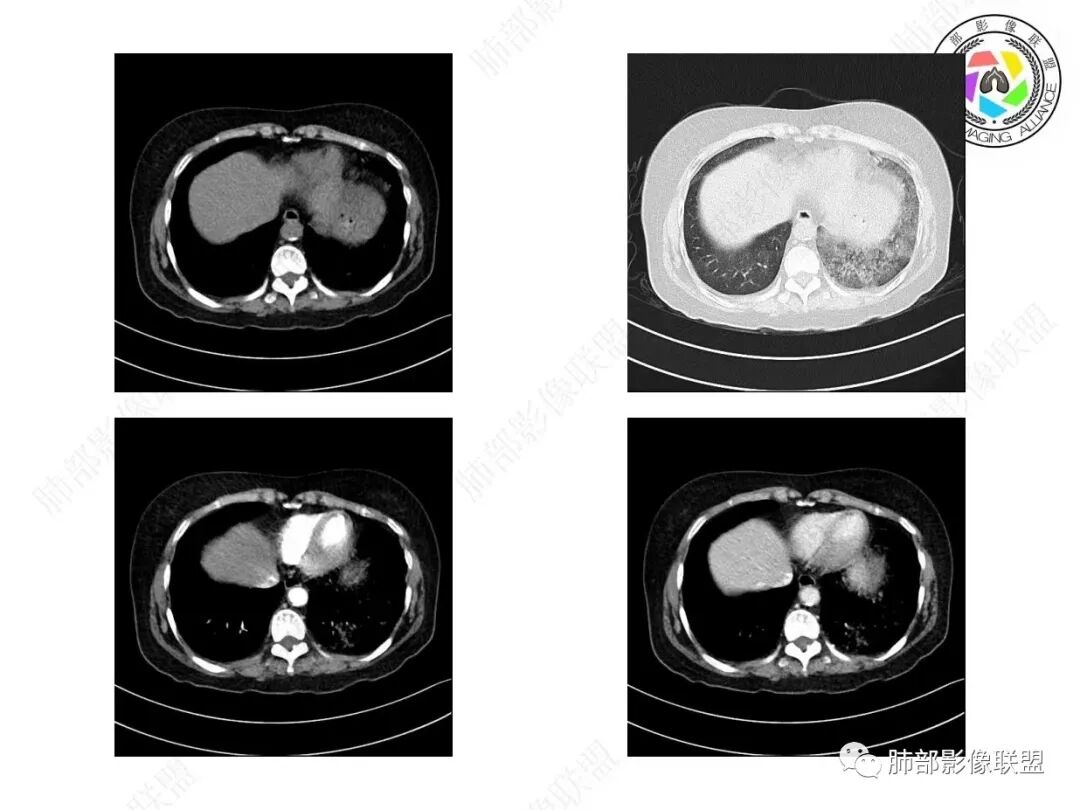

宇宙:两肺多发磨玻璃影,边缘模糊,左肺为著,左肺下叶伴实变,增强实变不均匀强化,其内支气管有阻塞、扩张,考虑粘液腺癌。

飞鹰行动:病史较长,左肺下叶实变及周围磨玻璃影,增强可见血管造影征,考虑左肺下叶粘液腺癌。

放射线:左肺下叶实变及双肺磨玻璃影,左下肺病灶周围磨玻璃影,有重力作用,呈叠瓦片状,增强可见血管造影征,考虑左肺下叶粘液腺癌伴双肺播散。

放射小白:中年女性,间断咳嗽一月余,咳痰4天;影像表现:右肺中下叶、左肺下叶见磨玻璃密度影,左肺下叶局部可见实性密度影,实性成分内部可见变窄、截断支气管通气征,增强实性成分内部可见血管造影征,但是血管扭曲,结合以上分析两肺符合肺黏液腺癌,不排除肺腺癌。

患者,女性,57岁。咳嗽1月、咳痰4天,亚急性病史,抗炎效果不佳,体温不高,痰为白色黏痰,白细胞稍高,主病灶在左下叶,实变+GGO,其余肺也有GGO,伴随有结节。

本例病例老年女性,慢性病程,抗炎效果不佳。CT示左肺下叶实变影,周围可见大片磨玻璃密度影,密度不均。右肺亦见少量斑片状磨玻璃密度影。增强可见血管造影征,结合南大分析,排除真菌,结核等,答案就呼之欲出了。